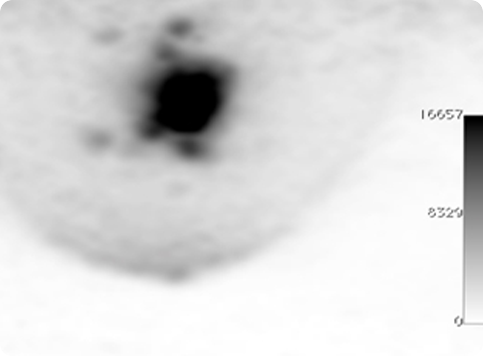

Figure 11

ClearPEM image of mini-Derenzo phantom illustrating the image resolution of 1.3 mm.